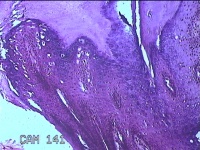

右侧拇指皮下结节

性别

男

年龄

40岁

临床诊断

皮下结节

一般病史

发现右侧拇指皮下结节1年余,无明显疼痛及不适。

标本名称

大体所见

灰白暗红色带皮肤结节0.8x0.3x0.2cm一个,表面糜烂,切开结节呈实性,切面灰白粉红色,质中。

图2